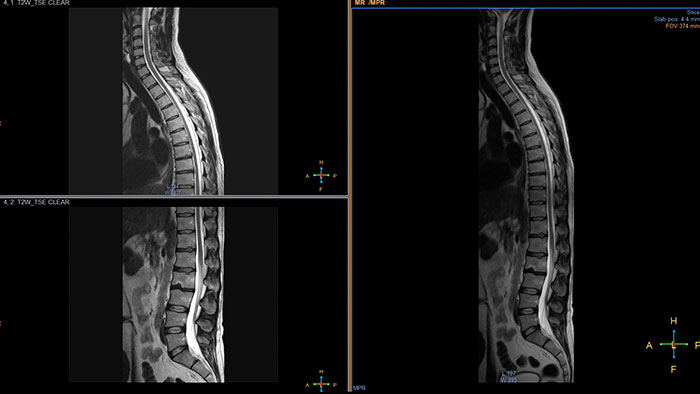

Automatic review of total body MR data

MR MobiView combines multiple images into a single full-field view to review multi-scanner acquisitions. MobiView is displayed with a single mouse click in the IntelliSpace Portal Multi Modality Viewer. Zero-click display is also available using predefined protocol. Key clinical cases are MRA run-offs, whole body metastases screening from eye-to-thighs, and total spine views to show the complete CNS. The resulting image series can be viewed, filmed, and exported using a DICOM compliant tool.

Benefits